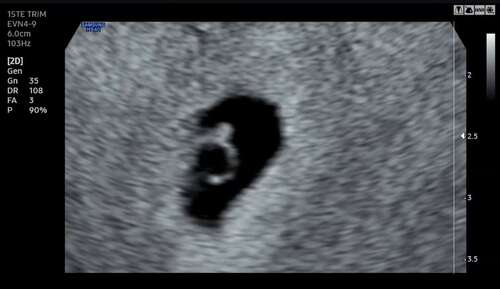

Vandaag met 7+0 goede echo & kloppend hartje gezien馃槂